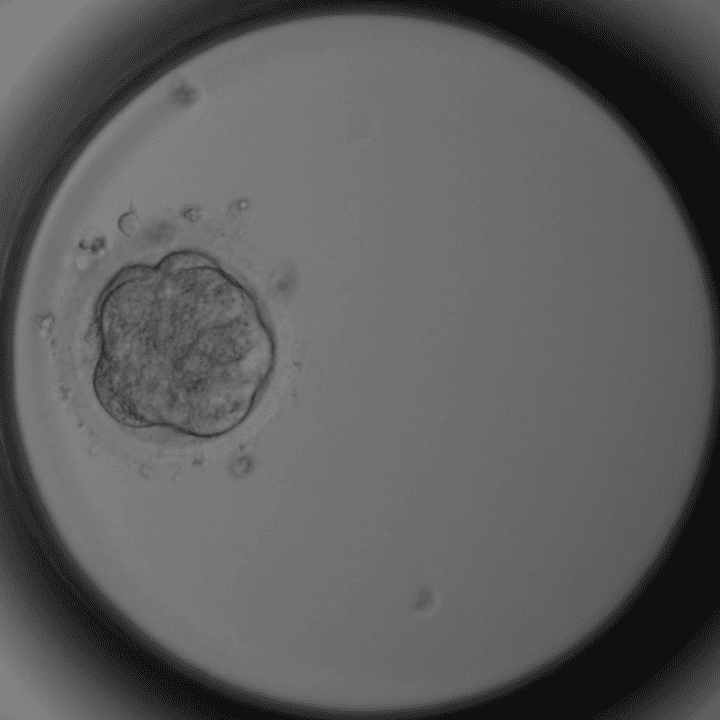

Tag 4 – Morula

Zellen verschmolzen, Blastozystenreifung beginnt.

Tag 5 – Blastozyste

100+ Zellen. Optimaler Zeitpunkt für Transfer oder Einfrieren.

Mikroskopaufnahmen aus unserem Embryologie-Labor in Thalheim bei Wels (Timelapse-Inkubator).

Nur die besten Embryonen werden transferiert oder eingefroren. Manche Embryonen entwickeln sich nicht weiter – das ist biologisch normal.

Dieser Artikel wurde von Dr. Roman Pavlik, Facharzt für Gynäkologie und Reproduktionsmedizin und ärztlicher Leiter der Kinderwunschklinik Dr. Pavlik in Thalheim bei Wels, verfasst. Die Embryo-Mikroskopbilder stammen aus unserem eigenen Labor – sie zeigen echte Entwicklungsstadien aus der täglichen Arbeit unseres Embryologie-Teams.